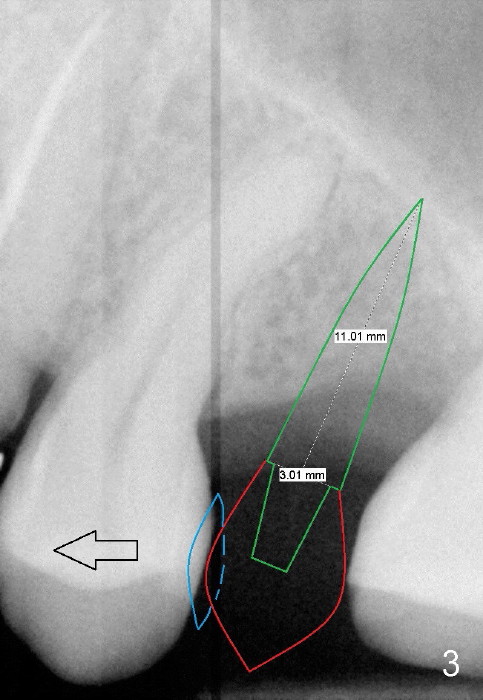

PA in Fig.1 is taken 8 months after exfoliation of the previous implant. It appears that the bone heals. One-piece implant (3x11 mm) is to be placed following tissue punch (Fig.2 green). If insertion torque is high, an immediate provisional will be fabricated (Fig.3 red). Once the implant osteointegrates, a rubber separator will be used repeatedly to move the 1st premolar mesially (arrow).

The 2nd option is to place 3.5 or 4x11 mm 2 piece implant. Try not to perforate the sinus floor initially, which causes infection, leading to implant failure. After 3 or 3.5 mm tissue punch (from DIO 1 piece implant kit), use 1.6 mm pilot drill, followed by 2.6 mm bone expander at the depth of 9 mm. Take PA after each step to confirm the depth. Use the implant to lift the sinus floor. If the latter fails, use 2.5 mm Bicon osteotome to do sinus lift with Osteogen, followed by implant placement. What is the intraop decision?